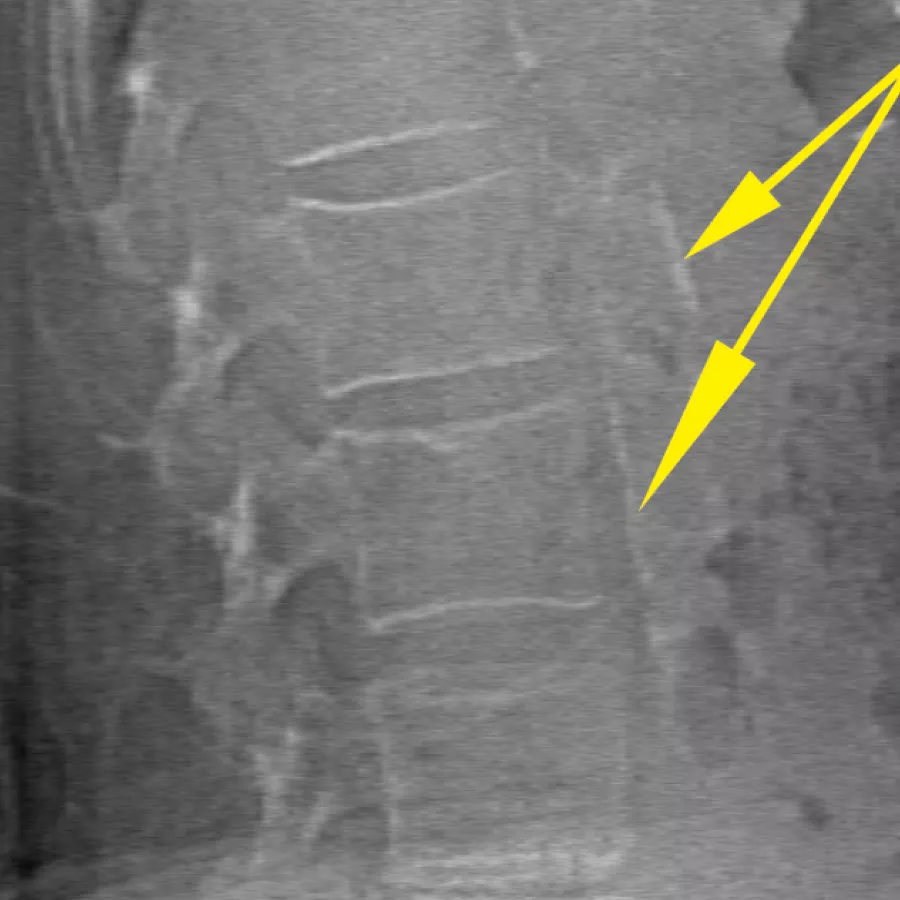

Évaluez le risque de fracture en associant une mesure précise de la densité osseuse à une imagerie vertébrale haute résolution. Vous pouvez identifier les fractures vertébrales en 10 secondes, à l’aide d’une image « à simple énergie » faiblement dosée.

Améliorez la précision et réduisez les erreurs d’analyse post-examen grâce à un positionnement précis et assisté par logiciel des espaces intervertébraux pour l’analyse graphique.